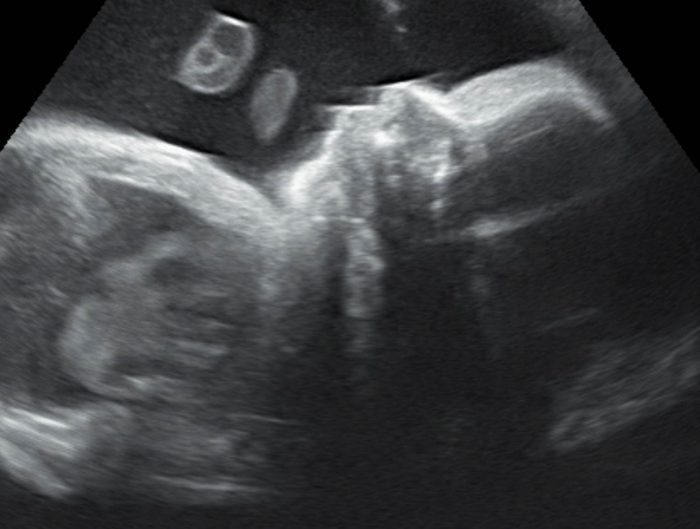

Baby Truitt was born prematurely on July 20, 2016. Before birth, he developed a condition known as non-immune hydrops and is currently in NICU. This blog will be providing periodic updates and prayer requests.